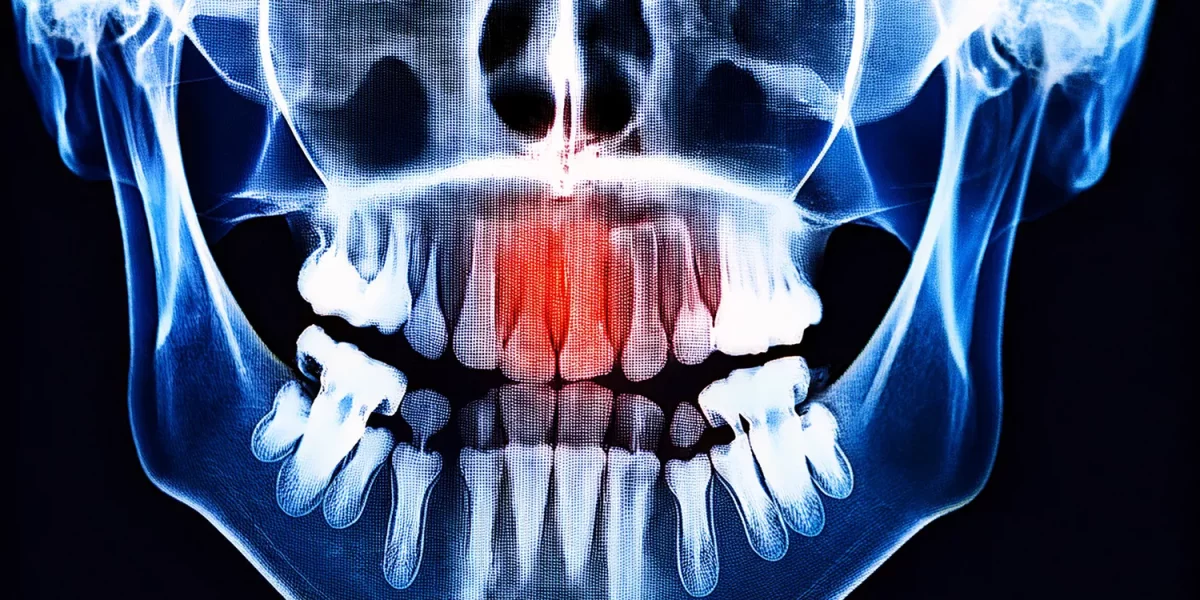

顎の嚢胞か腫瘍か?パノラマX線の「影」は何を意味するのか?

1. パノラマX線の「影」とは何か?

まず基本的なポイントを明確にしましょう。パノラマX線は歯科で最も一般的に使用されるスクリーニング用X線で、口全体と顎を一枚の画像で示します。

このフィルムでは:

1. 高密度で、ほぼ白く見える箇所: 通常は骨、充填物、金属、またはインプラントなどの構造です。

2. 低密度で、ほぼ黒く見える箇所: 骨密度が減少しているか「空洞」のような部分、例えば嚢胞性/腫瘍性/正常な空洞です。

したがって、報告書で言及されている用語:

「透過像」または「透過領域」とは単に「X線写真上で暗く見える領域」を意味します。

この暗い領域は時に:

1. 通常の解剖学的空間(例:副鼻腔腔)。

2. 正常な変異。

3. 歯に由来する顎の嚢胞。

4. まれに腫瘍性の形成。

したがって、「影がある」だけではがんがあるという意味ではありません。しかし、これは真剣に受け止め、口腔顎顔面外科医によって評価されるべき所見です。